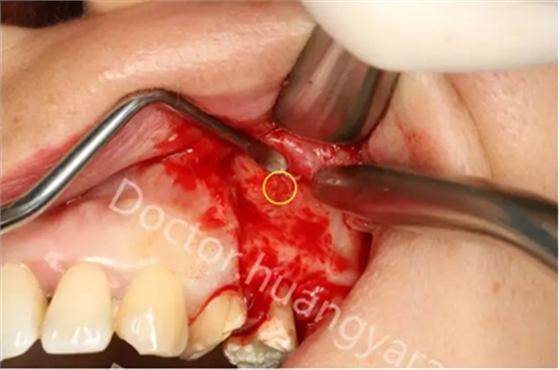

拍攝根尖片檢查,24、25牙根充到位,但考慮到可能是治療過程中消毒不到位導致,所以重新對25牙做根管治療,但酸痛感無減輕,于是考慮到根尖骨穿孔的可能性,與患者溝通后做診斷性翻瓣,翻瓣后發(fā)現(xiàn)根尖處無頰側(cè)骨板直接暴露,當即行根尖切除術(shù),對位縫合,經(jīng)兩個月恢復根尖已無酸痛感!